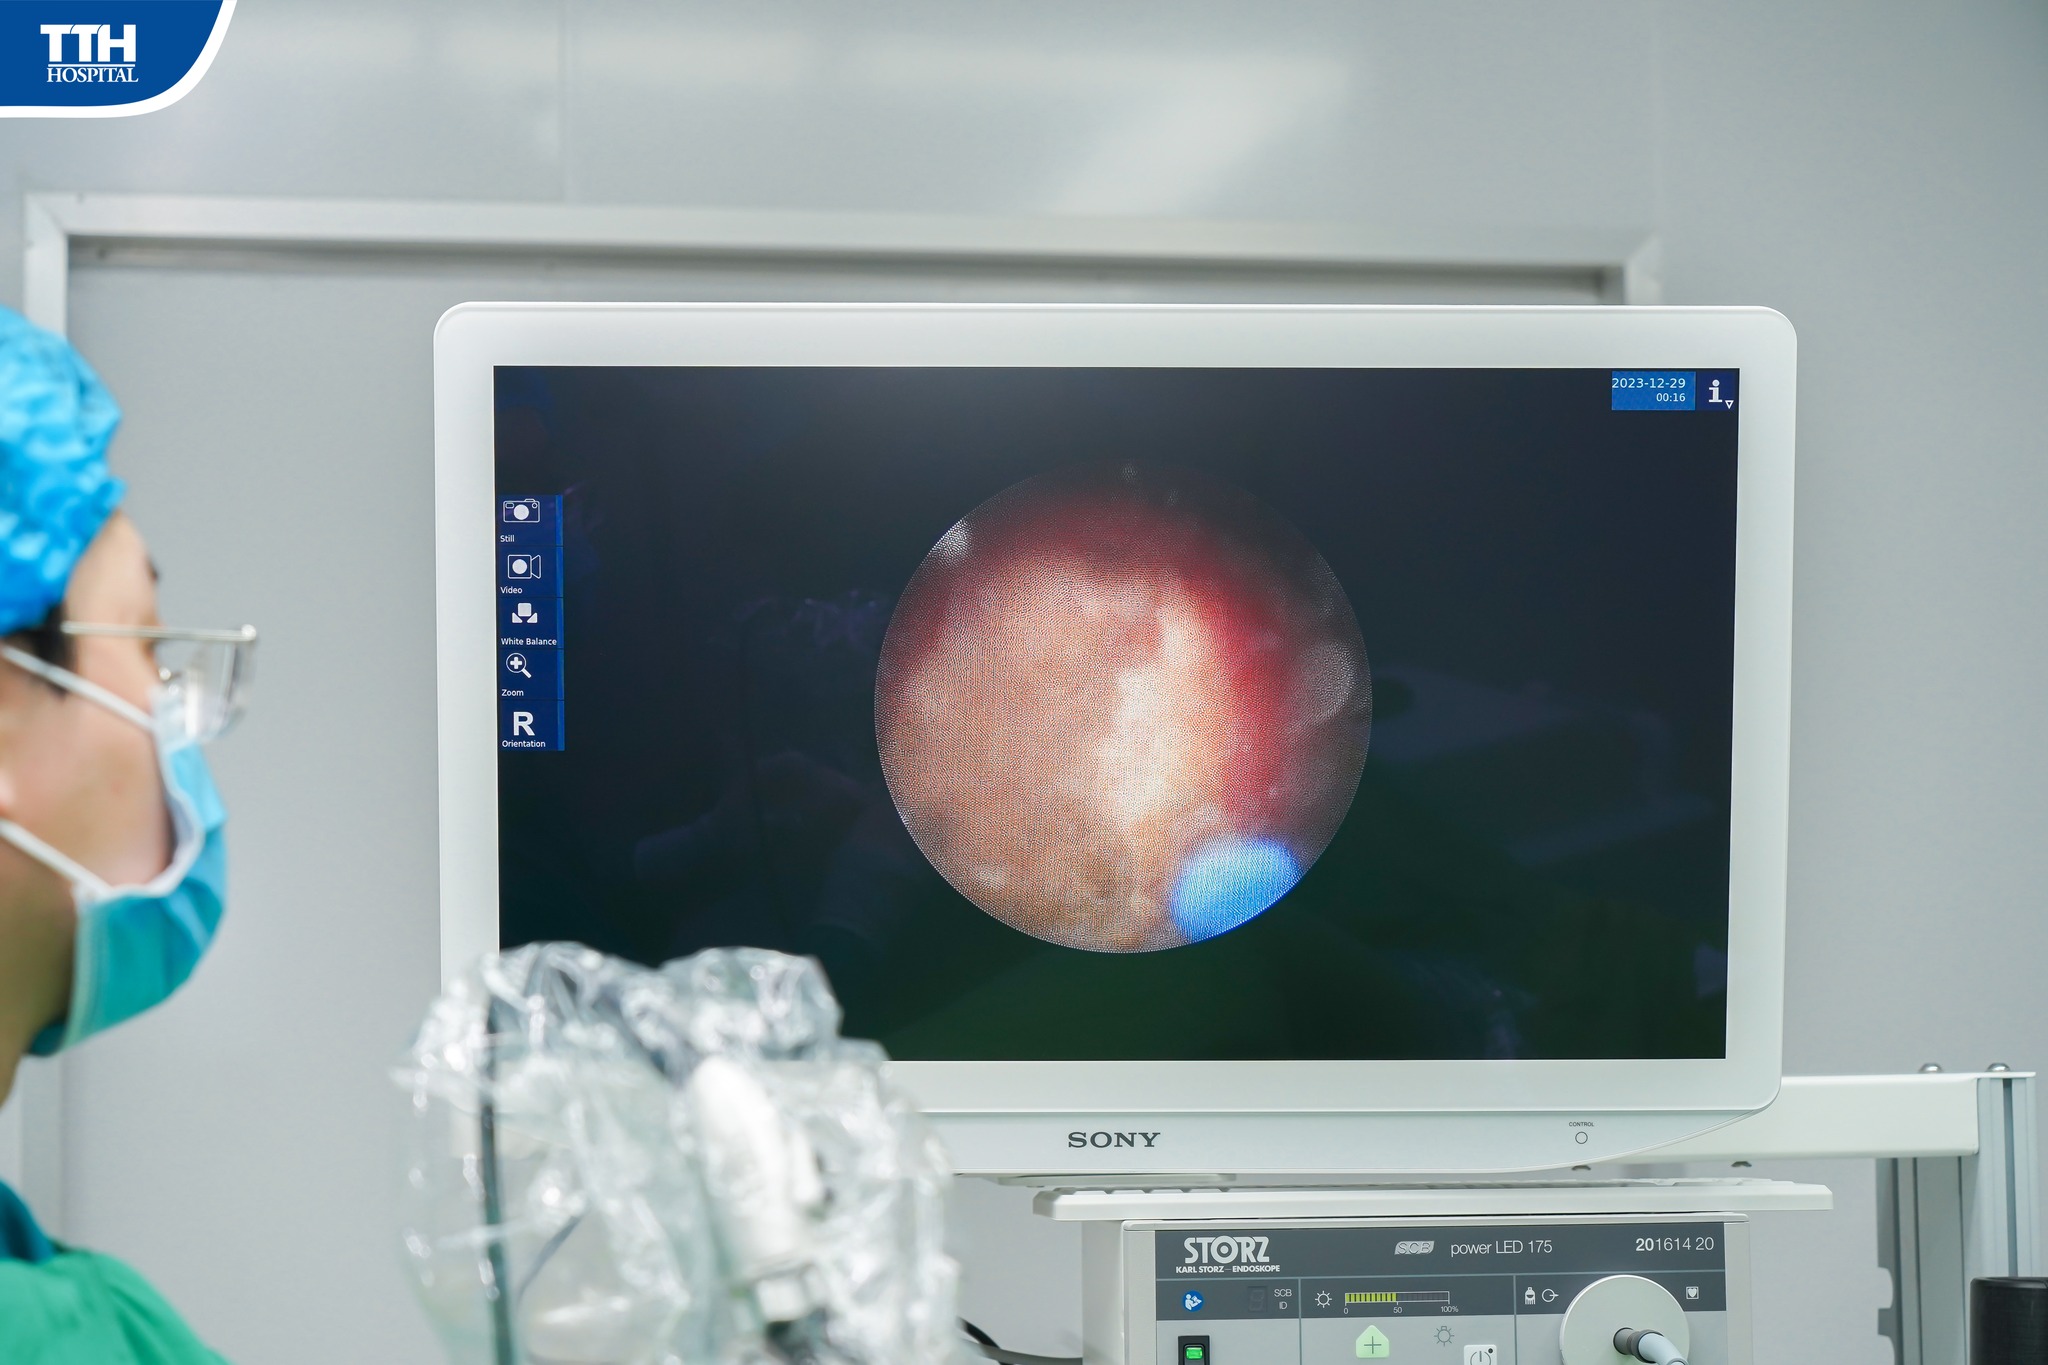

Bệnh nhân D.H.P (33 tuổi, Quảng Trạch) đến bệnh viện thăm khám trong tình trạng đau bụng vùng hông trái. Kết quả cận lâm sàng cho thấy sỏi vị trí khúc nối bể thận - niệu quản phải, kích thước 13mm làm thận phải ứ nước độ III và sỏi niệu quản trái 1/3 dưới kích thước 7mm làm thận trái ứ nước độ III. Các bác sĩ đã quyết định kết hợp 2 phẫu thuật nội soi sau phúc mạc lấy sỏi bên phải và tán sỏi ngược dòng bên trái nhằm lấy sạch sỏi, giảm thời gian nằm viện, tăng thời gian phục hồi cho bệnh nhân.

Bệnh nhân được ekip phẫu thuật của Th.S BSNT Võ Trường Giang - Phó Trưởng khoa Ngoại Tổng hợp Bệnh viện Đa khoa TTH Quảng Bình trực tiếp thực hiện. Kíp mổ đã thực hiện nội soi tán sỏi niệu quản trái trước, sau đó tiếp tục chuyển sang phương pháp mổ nội soi sau phúc mạc, bóc tách, xẻ niệu quản lấy nguyên viên sỏi ra ngoài qua vết mổ chỉ có 10mm.